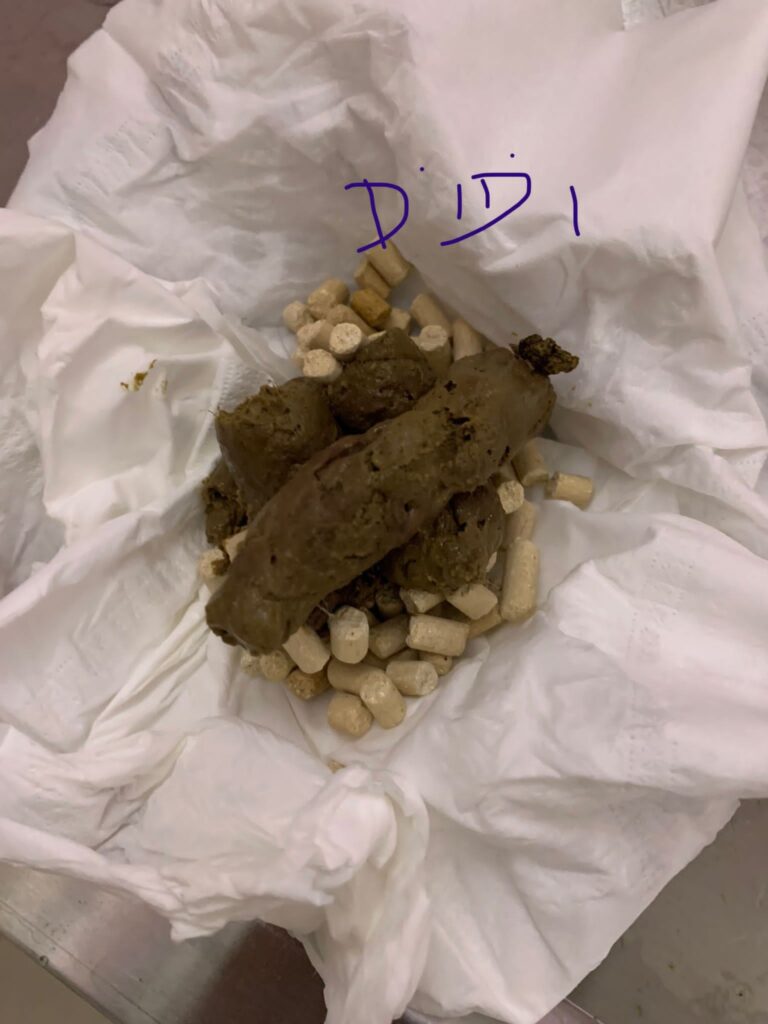

1pm: poo 4.5/10

Morning: didi constipated, saw him in 2 bins, trying to squeeze out something n can’t n he try to rub on floor – aren’t that pushing that piece in? I help him push out the 2cm piece 5/10, and he go to bin 03 and poo out another 12cm. So is that piece stuck n he is so uncomfortable. Subcut him w bupre also. His f patch still on. Can tear off soon. Need to buy more

Morning: sometime he will meow n meow at me. Want me sayang? In pain? Want some snacks? I sayang, f patch still on. I give him kelly n co fish don’t want, some Korean ciao like treat don’t want, given pidan prawn also don’t want. Have to think of what to bring over for him. Poo 4.5/10

Night: poo long n firm 5/10

7am+: he poo 1.5/10 w tinted blood. Reaction to niramine?

Morning: poo 3/10

Night: poo 1.5/10, w tinted blood

Night: poo 5/10, poo when i about to leave. Erm. Nice formed not much smell

Night: poo 3.5/10. Given him selar fish plate to munch after all the meds.

He poo 1.5/10, w blood (dr d says may be due to stress)

Poo 2/10 paste, given probiotics

Morning: poo like ice cream cone texture, small smelly!!